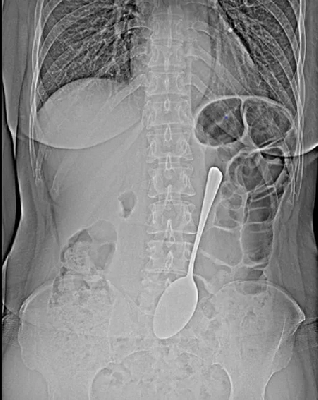

В Бурятии женщина, видимо, так увлеклась за обедом, что врачам пришлось выуживать из неё 18-сантиметровый столовый прибор.На помощь пришли врачи-эндоскописты. Они виртуозно провели операцию без единого разреза — достали ложку через эндоскоп.

— Инородные предметы могут спровоцировать перфорацию желудка, кишечную непроходимость. Если мелкие предметы вроде монет могут выйти из организма самостоятельно, то в случае со столовой ложкой всё могло быть серьёзнее", — комментирует врач-эндоскопист Валентина Бабудоржиева.